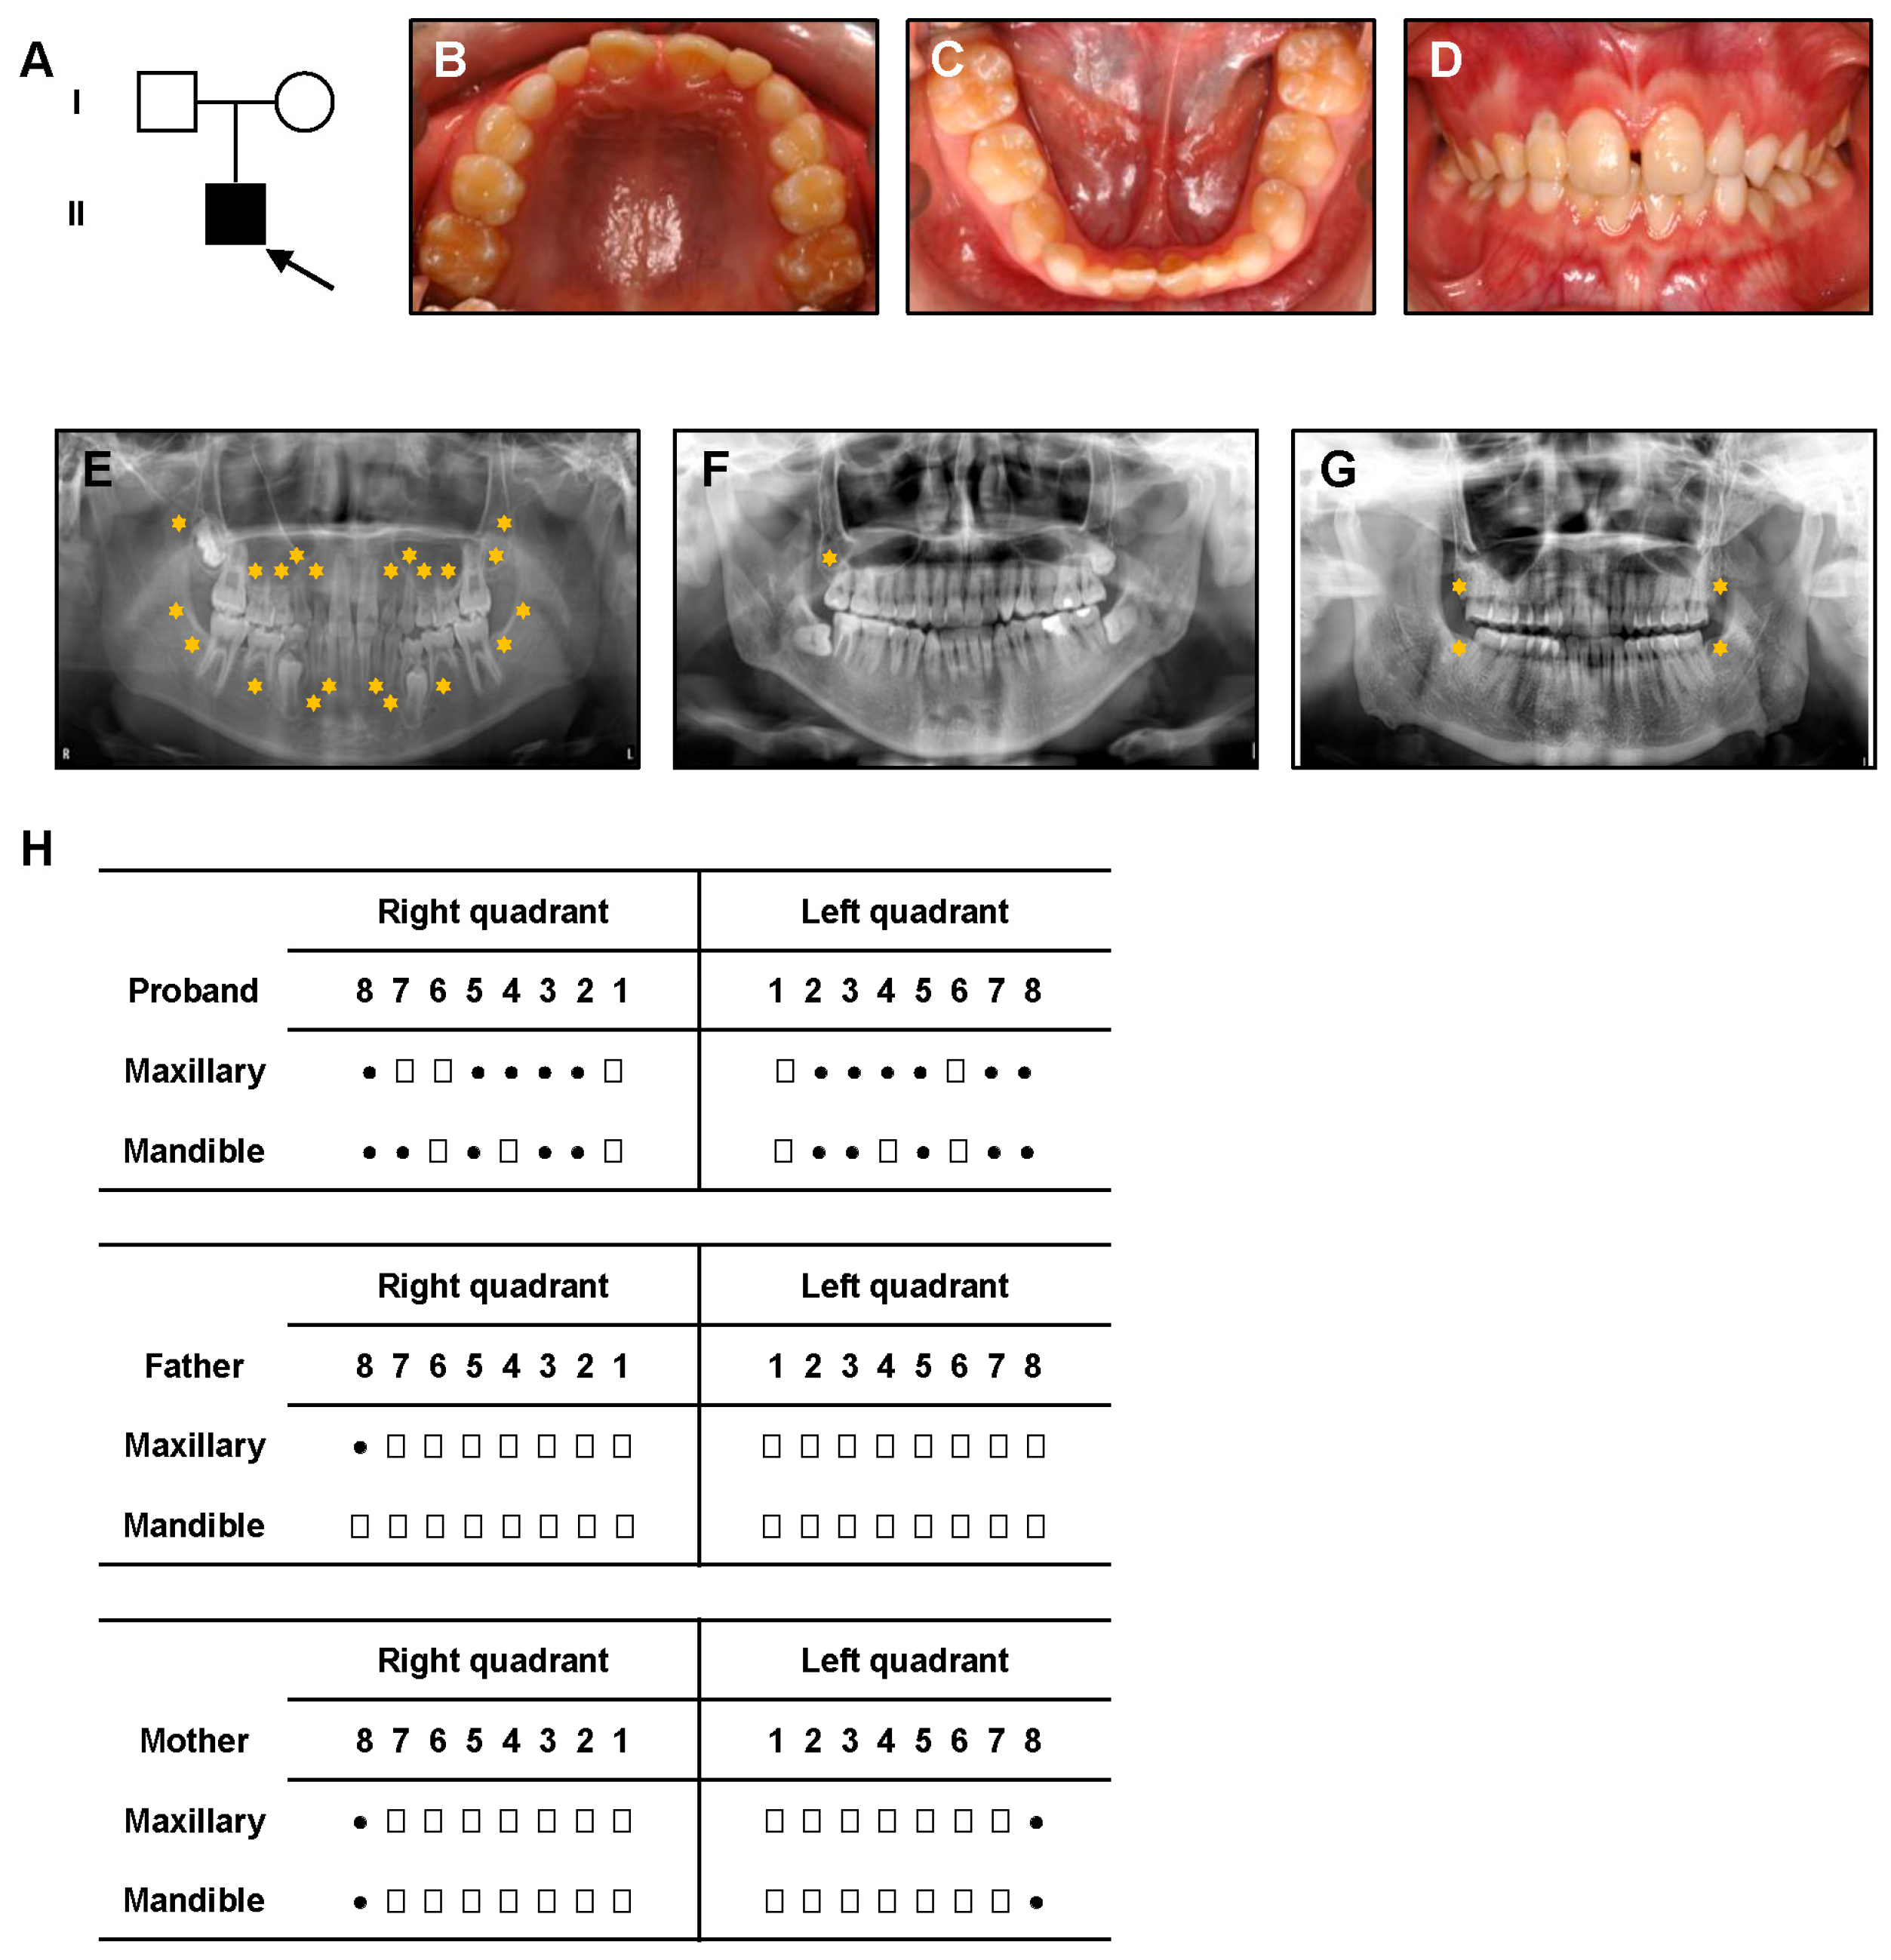

3.1. Clinical Manifestations

| Subject | Genotype | Phenotype |

|---|---|---|

| Proband | c.1657_1660delinsA | NSTA; absence of 17 permanent teeth |

| Father | Wild-type | Absence of 1 third molar (within normal variation) |

| Mother | c.1657_1660delinsA | No clinical anomalies; absence of third molars (within normal variation) |